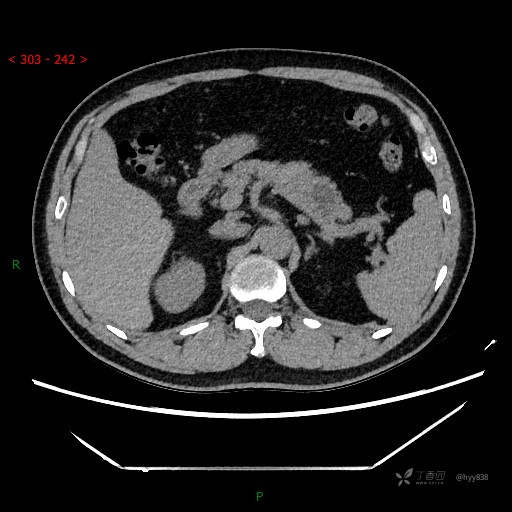

增强动脉期